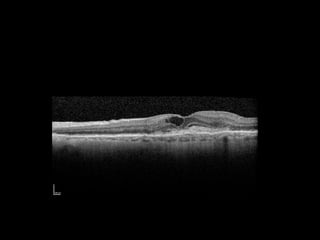

 Optical coherence tomography (OCT)

 Cross sectional image of the macula

AMD – KeyInvestigations  Optical coherence tomography (OCT)  Cross sectional image of the macula